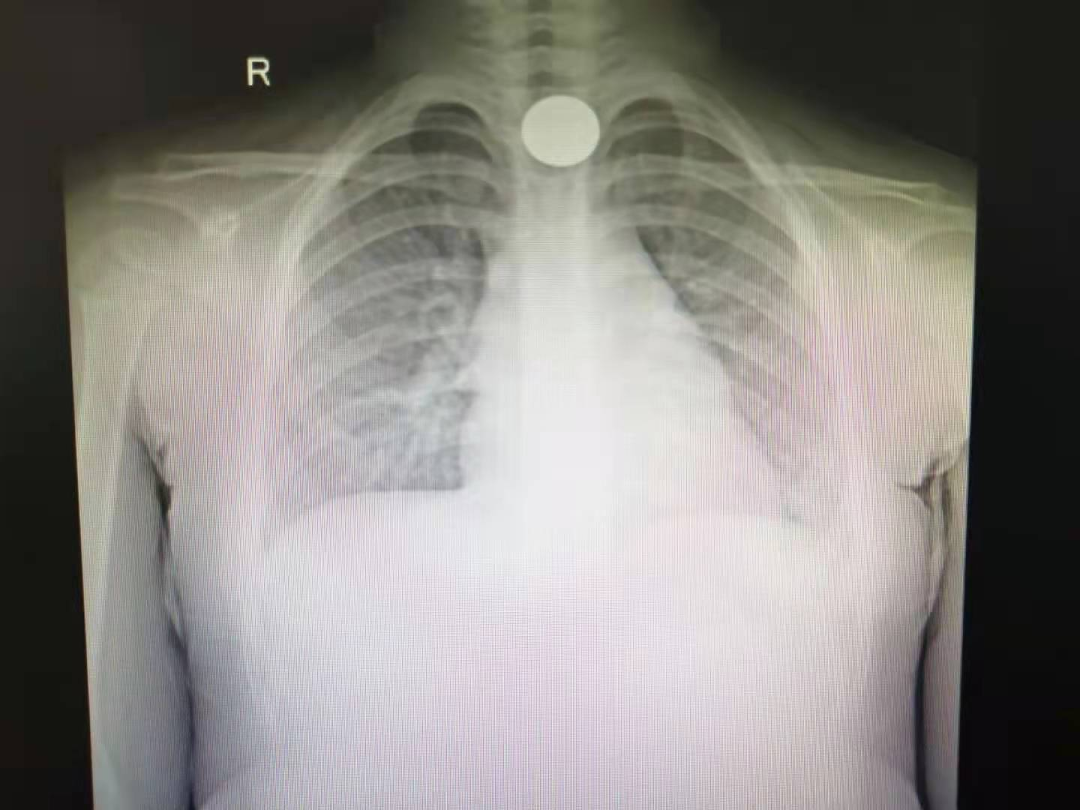

焦急!3岁儿童误吞硬币卡在食管入口处

近日,家住茂名市区的三岁小女儿琳琳(化名)在玩耍时不慎将一枚5角的硬币误吞入口中,当家长发现并送到茂名市人民医院耳鼻喉科时,距离异物吞入已经接近13个小时。耳鼻喉科专家紧急会诊并确定治疗方案,完善相关术前检查并征得家长同意后,采用插管全麻下行食管镜检查+异物取出术,短短仅5分多钟便将硬币顺利取出,让孩子转危为安。这枚5角硬币,着实让小琳琳家人捏了几把汗。